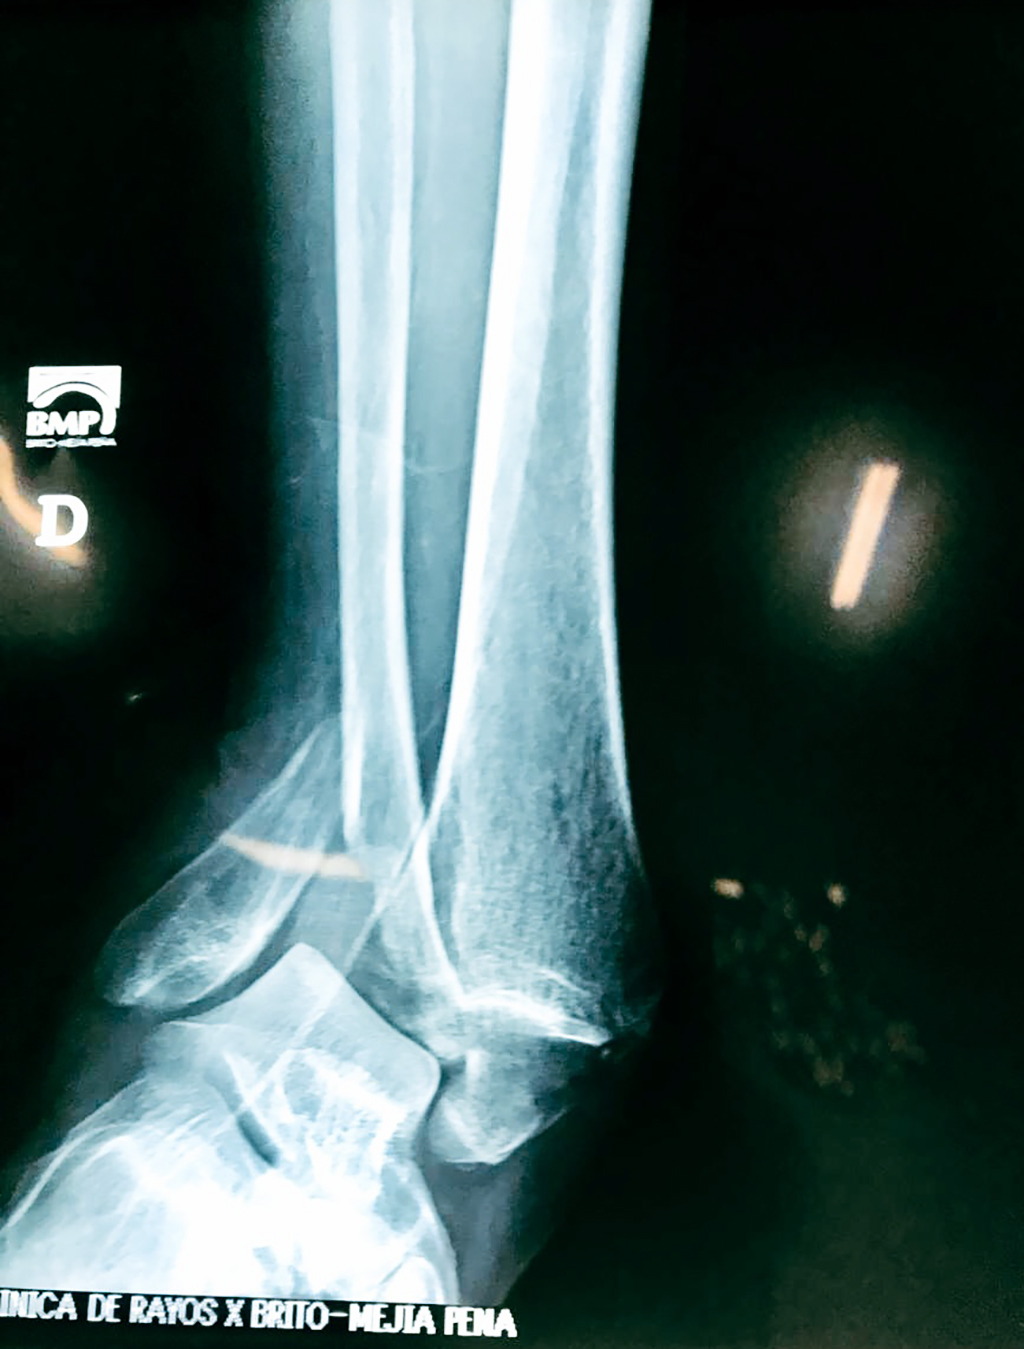

Cirugías de Tobillos

Cuando se necesita cirugía, es probable que esta implique el uso de clavijas de metal, tornillos o placas para sostener los huesos en su lugar mientras la fractura se consolida. Los elementos de soporte pueden ser temporales o permanentes.